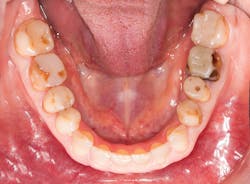

A patient presented with multiple deficient restorations, discolored teeth, and attrition (figures 1–4). The patient’s treatment plan was a full-mouth rehabilitation with a combination of veneers, crowns, and onlays.